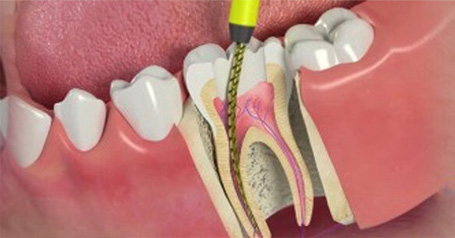

A root canal is a dental procedure that removes the infected or damaged pulp from inside your tooth, cleans and disinfects the area, and then seals it. This helps save your natural tooth and prevents the need for extraction.

A root canal is a dental procedure that saves a damaged or infected tooth by replacing the tooth's pulp with a filling and is the most common treatment for a tooth ache that is severe and caused by nerve irritation . It's also known as endodontic treatment. Rootcanals almost instantly relieve a long standing or severe toothache that is caused due to nerve irritation or infection . There is a mystique surrounding Root Canal Treatments, and the reality is that they are not half as bad as people think.

4. Shaping & Filling the Root Canals

The infected pulp is removed and the tooth is filled with root filling

If the nerve of a tooth has become decayed or infected, a Root Canal may save the tooth itself whilst removing the problematic root. The nerve part of the tooth, along with the pulp (living tissue inside the tooth) and any bacteria or decay present is removed; then the tooth is sealed with special root-filling cement all the way to the tip of the root. This will save your tooth once the root is filled and sealed properly to the very apex; and it gets rid of the painful soft tissue and leaves a hard shell. A dental crown is then fitted to ensure the tooth has full functionality within your mouth.